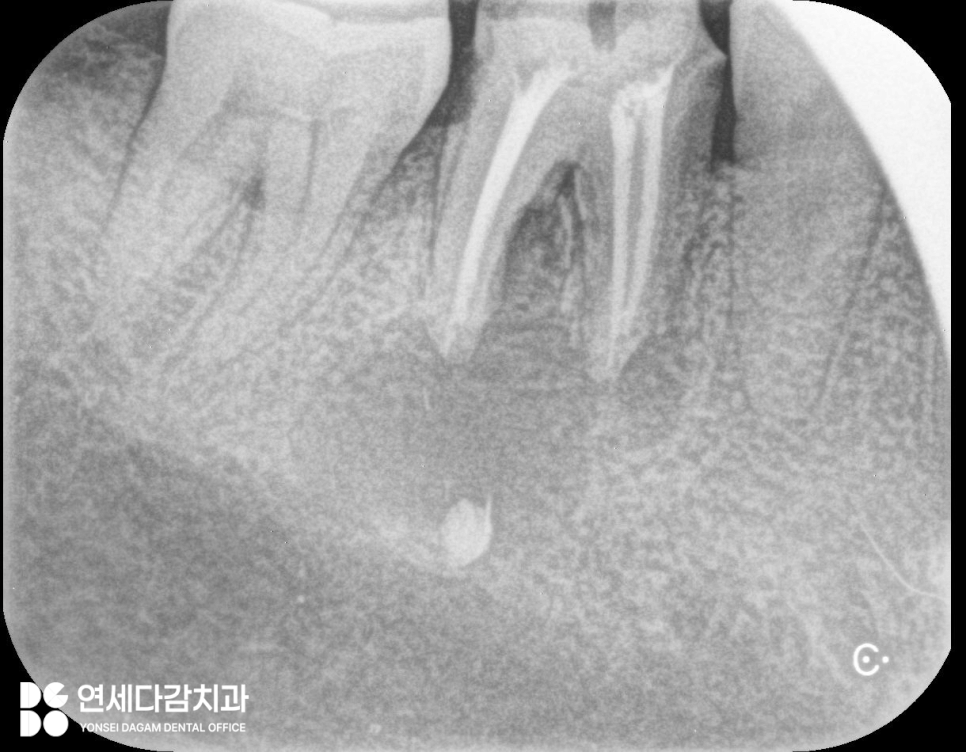

엑스레이 촬영을 하면 투과성으로

치아 뿌리 끝에 검은 그림자처럼

나타나는 것이 특징입니다.

이 병소에는 여러 종류가 있지만

그중에서도 치근단 낭은

흔하게 발견되는 형태입니다.

치근단 낭(Periapical cyst)

치근단 낭은 액체나 반고체 물질이

담긴 주머니 형태로,

뿌리 끝 주변 뼈를 점차

파괴하면서 커지게 됩니다.